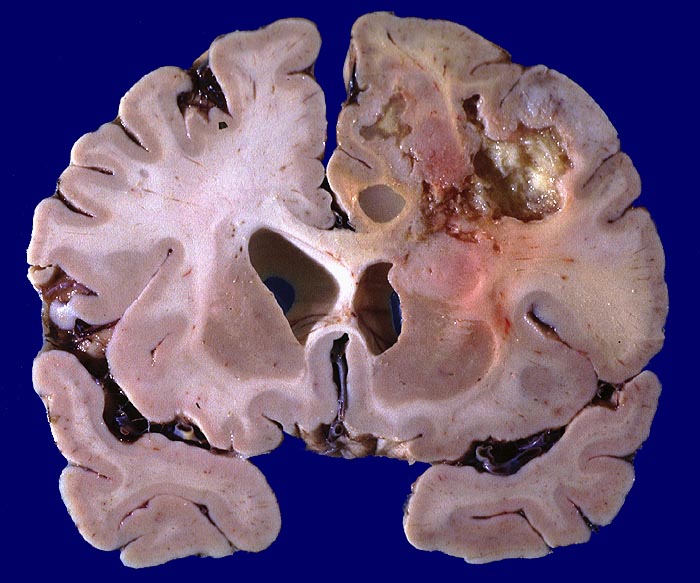

Morphologie:

Die Schnittfläche ist auffallend bunt. Dies ist bedingt durch ein Nebeneinander von graurotem vitalem Tumorgewebe, gelben Nekrosen, roten Einblutungen und gelegentlich grünlichen Gallertzysten.

• Zellreicher Tumor mit sehr unscharfer Begrenzung zum normalen Hirnparenchym (rechts unten).

Makroskopie

Pathologischer Befund